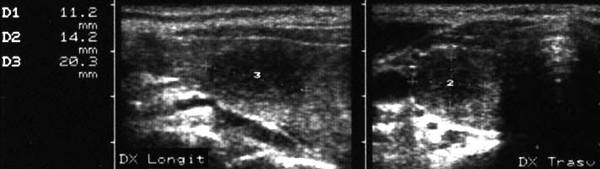

Apexul lobului drept, proiectie longitudinala si trasversala.

Femeie 58 ani. Maladia Graves in tratament cu

metimazol.

Nodul unic in apexul lobului drept, de 11x14x20mm (1,5 cc), hipoecogen, cu

contur difuz

Nu s-a efetuat citoaspiratie.

Aceeasi pacienta. La ecodoppler color - vascularizatie

periferica, avascular intralezional.

Ecopowerdoppler confirma absenta vascularizatiei interne.